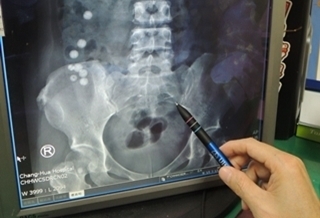

(優活健康網記者徐平/綜合報導)生鏽鐵釘穿腸卡肚2年竟沒事!一名疑有精神障礙的44歲婦女,日前因吞食小彈珠到院就診,神奇的是腹部除了有8顆彈珠外,竟然還有一根已斷成兩截的生鏽鐵釘卡在腹腔內,拒患者陳述該鐵釘在腹腔內2年都沒有排出,但卻沒引發腹膜炎等疾病,醫師利用腹腔鏡手術,取出小腸外、腹腔內的網膜處的2公分長的生鏽鐵釘。照射X光發現 體內有圓球物及不明物體彰化醫院肝膽腸胃科主任陳詩典表示,該名婦女吞了多顆彈珠,經照射X光發現,小腸處有8顆約1公分直徑的圓球物,而後病人又提及曾在2年前吞下鐵釘一直沒有排出,經仔細觀看X光,腹腔內確有兩段不明物體,經電腦斷層確認為外來物。外科主任余明昌表示,一般而言,異物入肚最多的東西是大根的魚刺,外來異物刺穿小腸,會造成腹膜炎,若不馬上處理,還可能演變成敗血症,有生命危險,但該起個案,鐵釘刺穿小腸後,小腸卻自行癒合,沒引發後續的腹膜炎,而鐵釘就待在體內達2年,又不會疼痛,相當罕見。異物入口要馬上就醫 由醫師評估處理陳詩典說,吞進異物都有機會從肛門排出,如果位置在內視鏡可取出的食道、胃、直腸等處就可直接以內視鏡取出,如果已經到了小腸,就只能等待排出,若觀察3天無法排出或產生腹痛,就得考慮手術取出。陳詩典強調,此件個案的鐵釘卡在肚子內長達2年,萬一鐵釘又被擠壓到其他器官,難保不會有生命危險,因此,不會消化的異物入口應該要馬上就醫,由醫師來評估後續處理方式。余明昌主任表示,異物入肚的病人以精神疾病患者最多,小孩子也常誤食,家人應多加關心。